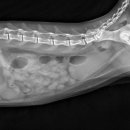

근처 목동근처에 로운동물병원이 있어서 전화예약을 하고 가게 됐는데, 그 전에 우선 부천 병원에 먼저 가야합니다 이유는? 수술을 받은 곳에서 수술이 잘 된 걸 확인해야 하고 (타 병원에서는 수술을 자기 병원에서 하지 않았을 때 문제가 생기면 책임 질 수 없기 때문이라는 겁니다) 복잡하지요.... (등에 있는 건...